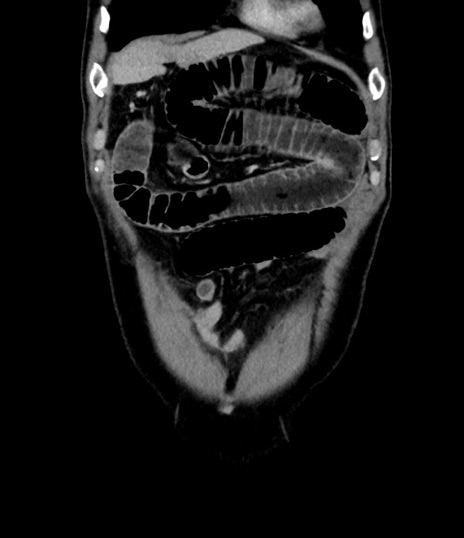

症例8(冠状断像)

【症例】 60歳代男性

【主訴】 黒色吐物

【現病歴】 4日前から嘔気自覚、2日前の朝食後にも嘔気あり、自分で手で嘔吐反射起こし嘔吐したところ血が混ざっていたため受診。

【既往歴】 5年前汎発性腹膜炎を伴う急性虫垂炎で手術、高血圧、前立腺肥大症、高脂血症

【身体所見】 腹部正中に手術癩痕あり 腹部平坦・軟圧痛なし膨満感あり

【データ】WBC 8400、CRP 4.54